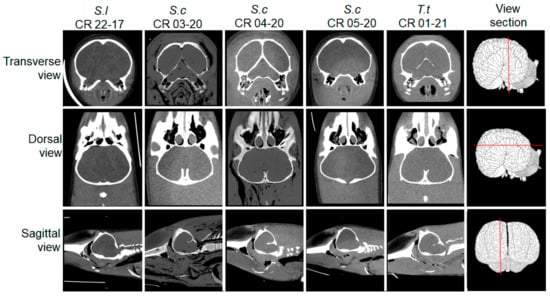

| Code | Species | Age | Sex | Stranding | Ocean | PMCT Days b | RBT/ cELISA | B. cetic |

|---|---|---|---|---|---|---|---|---|

| CR 22-17 | Stenella longirostris | C | M | 2017 | P | 10 | Negative | Negative |

| CR 03-20 | Stenella coeruleoalba | A | M | 2020 | P | 0 | Negative | Negative |

| CR 04-20 | Stenella coeruleoalba | A | F | 2020 | P | 3 | Negative | Negative |

| CR 05-20 | Stenella coeruleoalba | C | F | 2020 | P | 3 | Negative | Negative |

| CR 01-21 | Tursiops truncatus | A | F | 2021 | P | 0 | Negative | Negative |